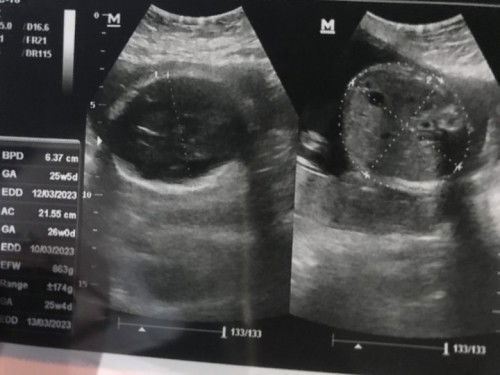

dokternya bilang gmn bun? krn di UK 25w itu kalo ada cairan berlebih udah keliatan dan harusnya dokternya bilang